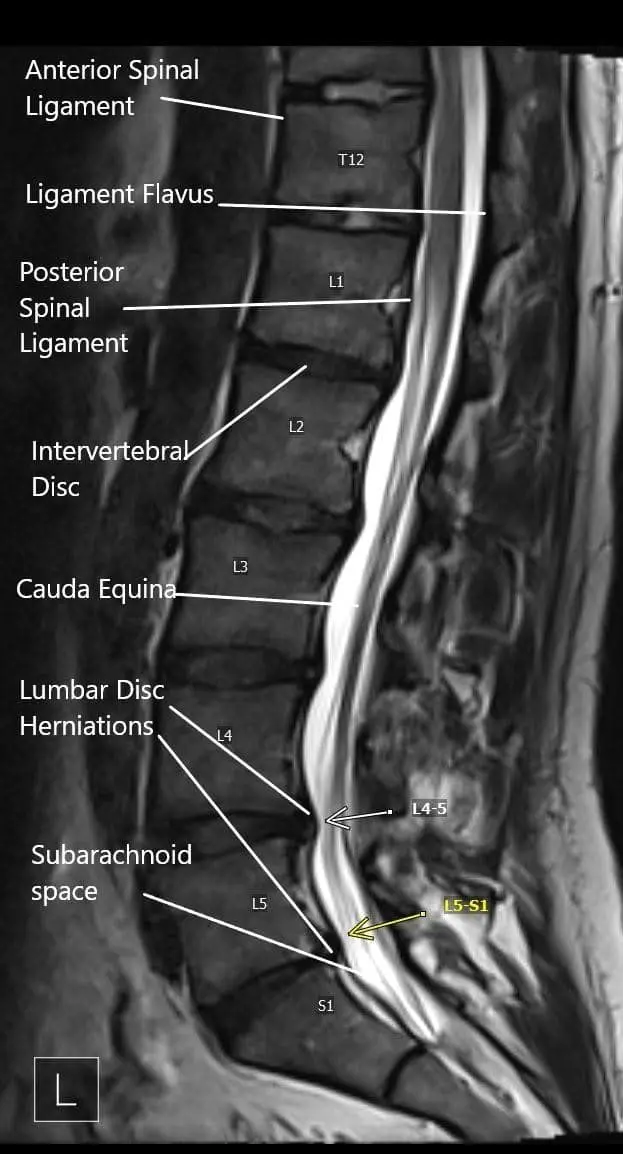

Sagittal section of the lumbosacral on MRI.